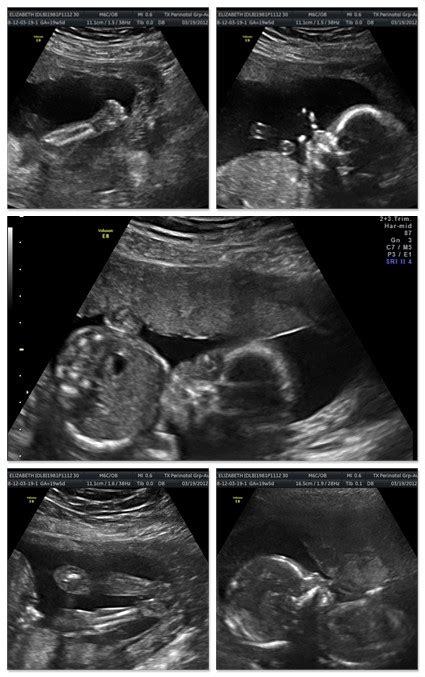

18- 42 Week Scan | Ultrasound to determine Placental ...

18- 42 Week Scan | Ultrasound to determine Placental ... from ultrasoundcare.click2cms.com.au

By 18 to 20 weeks, the placenta weighs about 5 ounces. During pregnancy, your body needs more iron to keep up with your expanding blood volume as well as to nourish your growing baby and the placenta. More images for how big is a placenta at 20 weeks » Pregnancy checklist at 20 weeks. If the placenta isn't delivered within 30 minutes after childbirth, it's known as a retained placenta. Is there anybody having grade 4 placenta previa. At 24 weeks, the placenta is around 24 millimeters thick, and so on. It's considered mature by 34 weeks. At 20 week scan it was fundo anterior placenta grade 0. The placenta continues to grow along with the uterus throughout the second trimester. At around 20 weeks of pregnancy, the top of the uterus reaches the navel, and your fundal height would be about 7 to 8.5 inches (18 to 22 centimeters). During this ultrasound, the doctor will make sure that the placenta is healthy and attached normally and that your baby is growing. By week 12, the placenta is formed and ready to take over nourishment for the baby.

Is there anybody having grade 4 placenta previa. A fetus that's 20 weeks along would be nurtured by a placenta about 20 millimeters thick. If the placenta isn't delivered within 30 minutes after childbirth, it's known as a retained placenta. At 24 weeks, the placenta is around 24 millimeters thick, and so on. An ultrasound is usually done for all pregnant women at 20 weeks. More images for how big is a placenta at 20 weeks » At around 20 weeks of pregnancy, the top of the uterus reaches the navel, and your fundal height would be about 7 to 8.5 inches (18 to 22 centimeters). However, it continues to grow throughout your pregnancy. At 20 week scan it was fundo anterior placenta grade 0. In most women, growth slows in the third trimester as your baby maxes out the space in the womb. Your fundal height in centimeters is roughly equal to the number of weeks you are pregnant! During pregnancy, your body needs more iron to keep up with your expanding blood volume as well as to nourish your growing baby and the placenta. Beans, beef, and fortified cereal are good sources.